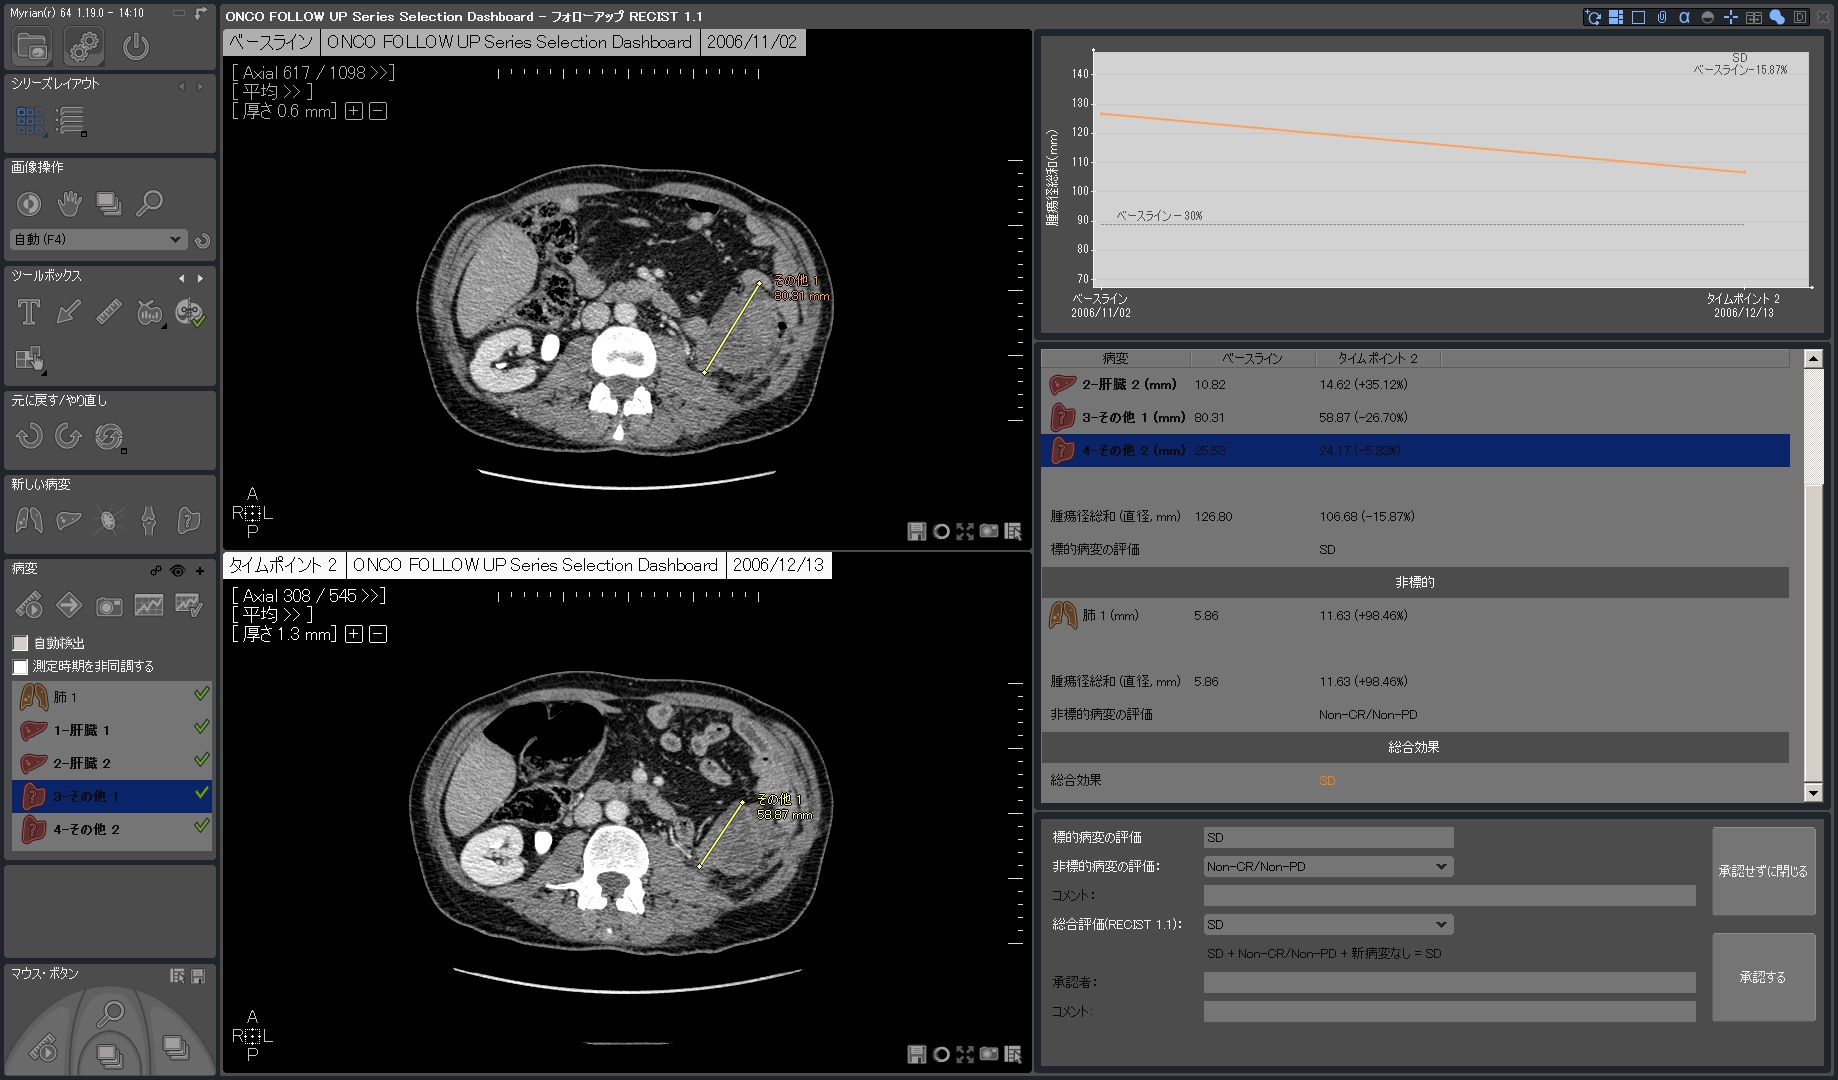

| 4.ダッシュボードでレスポンスグラフと一覧表を素早く確認 | |

フォローアップに必要なすべてのステップは自動化されています。 ベースライン作成後、次のタイムポイントでは自動的に非剛体レジストレーションが行われ、高速な検査比較が可能です。必要に応じて自動で国際評価基準(RECIST1.0,1.1)に沿った治療レスポンスが計算され、PACSへ転送されます。そし検査レポートも自動作成されます。